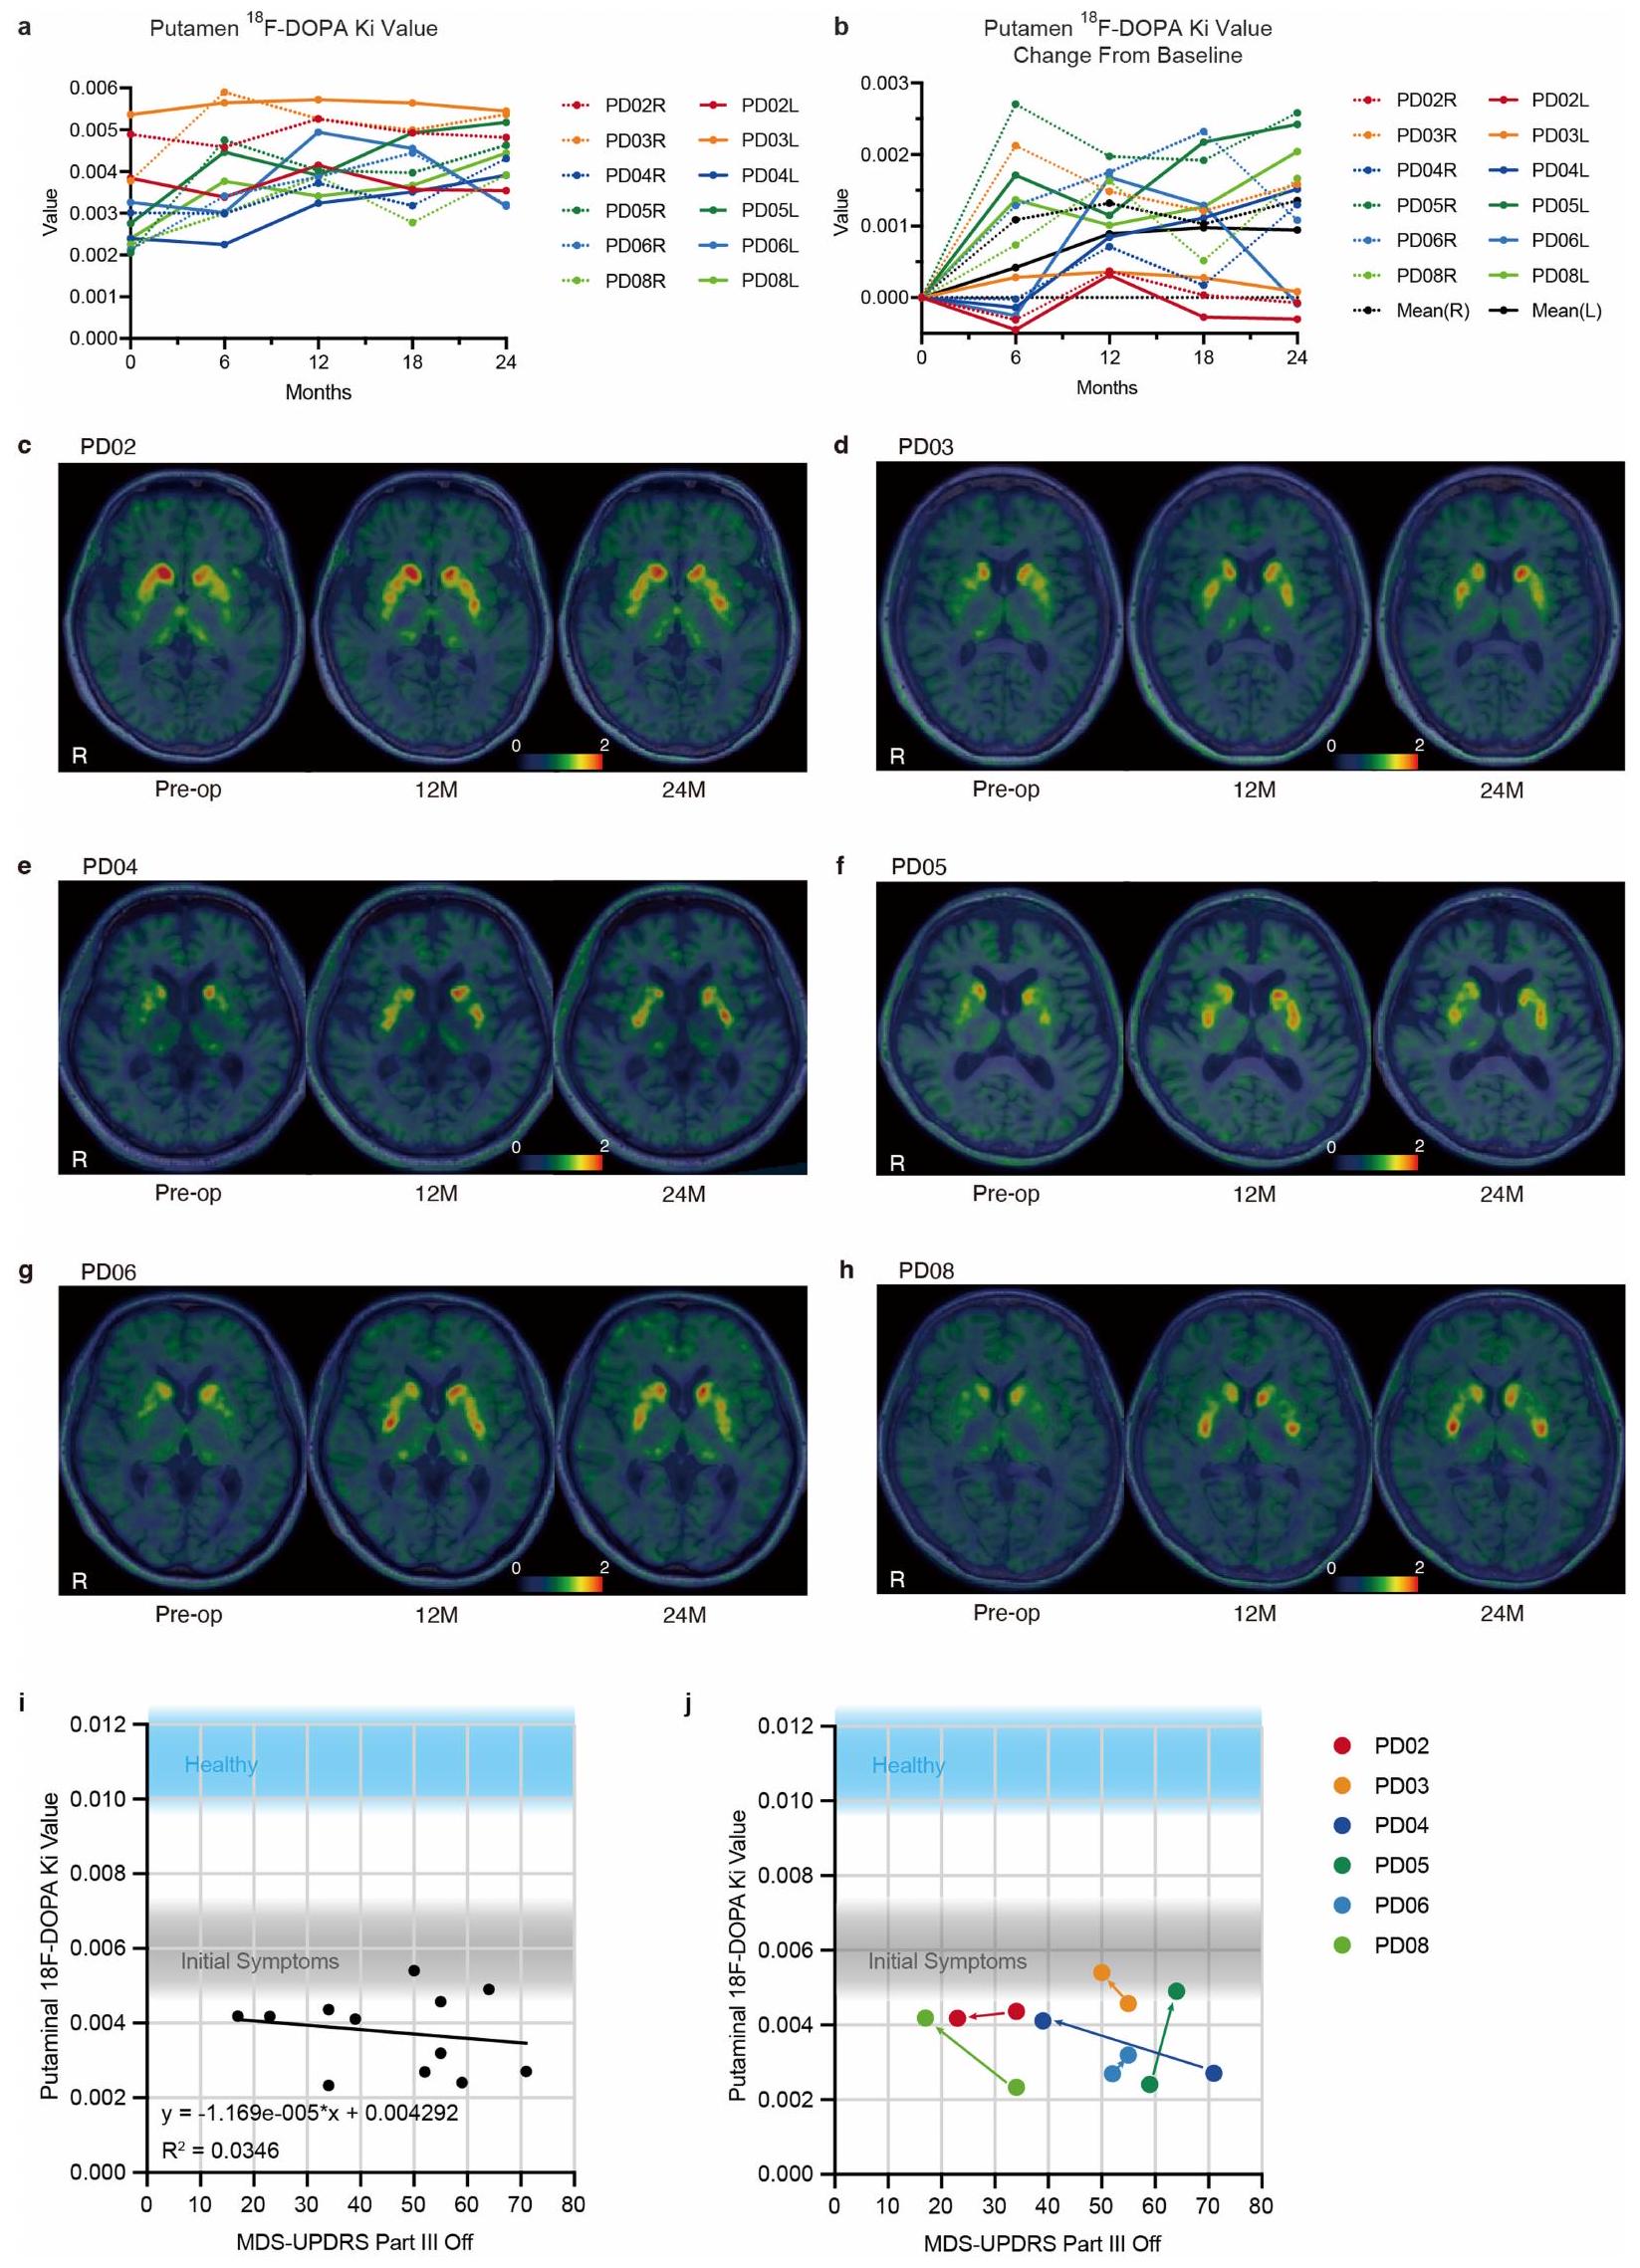

Efficacy evaluations revealed that four out of six patients showed improvements in the Movement Disorder Society Unified Parkinson’s Disease Rating Scale part III OFF scores, with average changes of 9.5 points (20.4% improvement) and 4.3 points (35.7% improvement) in the ON scores. Additionally, Hoehn-Yahr stages improved in four patients, and the influx rate constant ($K_i$) values in the putamen increased by 44.7%, particularly in the high-dose group. The trial demonstrated that the transplanted iPS-cell-derived dopaminergic progenitors survived, produced dopamine, and did not form tumors, suggesting both safety and potential clinical benefits for PD treatment.

The phase-I/II trial (jRCT2090220384) conducted at Kyoto University Hospital aimed to evaluate the safety and efficacy of striatal transplantation of allogeneic induced pluripotent stem cell (iPS-cell)-derived dopamine (DA) progenitors in patients with Parkinson’s disease (PD). A total of seven patients underwent bilateral transplantation, with three receiving a low-dose and four a high-dose of DA progenitors. Over a 24-month follow-up, the trial reported no serious adverse events, and the majority of adverse events were mild and transient. Notably, four out of six patients demonstrated significant improvements in motor function as assessed by the MDS Unified Parkinson’s Disease Rating Scale (MDS-UPDRS) part III during off-time periods, indicating functional integration of the grafted cells as DA neurons.

MRI assessments revealed a gradual increase in graft volume without evidence of tumor formation, supported by histological analyses showing minimal cellular proliferation. The trial’s findings suggest that iPS-cell-derived DA progenitors can survive and functionally replace lost DA neurons in PD patients, with a favorable safety profile. However, the study’s limitations include its open-label design and small sample size, necessitating further investigation through larger, controlled trials. Overall, the results indicate that allogeneic transplantation of iPS-cell-derived DA progenitors is a promising regenerative therapy for PD, warranting exploration of combined therapeutic strategies to enhance efficacy.